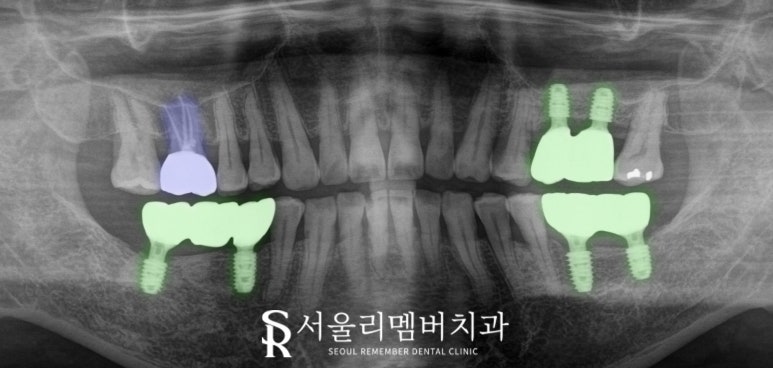

첫날 임플란트 인상 채득(본뜨기)를 하고

보철이 제작되기까지

며칠이 소요되며,

제작 이후 구강 내에 장착해 본 뒤

혹시나 불편하시거나 개선하고 싶은 부분이 있다면

조정하여 편안한 교합을 맞춰드려야 되기 때문이죠.

이 케이스는 최종 보철 세팅 후

일주일 정도 더 머무르시며

교합 조정만 살짝 해드리고

마무리했는데요,